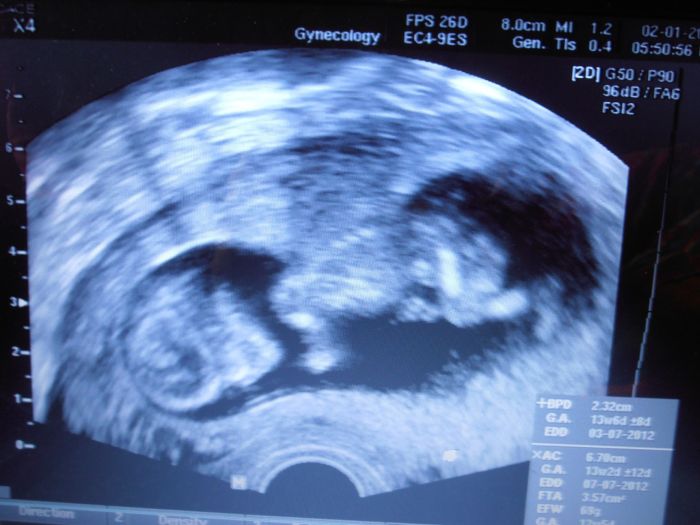

Tak jsem po kontrole, dnes naštěstí nekrvácím ani nešpiním, ježiši, kéž by už. Mimi v pořádku máme pětiminutové video z utz :-) paráda, máme spočítané i prsty na ručičkách , cucalo si palec, nádhera. To krvácení prý ten možná z nízko položené placenty, ale dr. mě téměř zdrbal, že to nemám řešit, že prostě když krvácím, tak si mám lehnout a neřešit to. že je zbytečné jezdit někam na pohotovost. A mám vysoký tlak, příště mi dá asi nějaké léky na snižování.

Hlavně odpočívej.Máš krásnou fotečku,jak má pokrčené nožičky

[71102] To je tááák krásný. Už abych v tom stadiu byla taky! Jsem ted dle poslední ms 8+2, tak jsem pořád napnutá, jak to se mnou po mých předešlých 3 potratech dopadne??!!